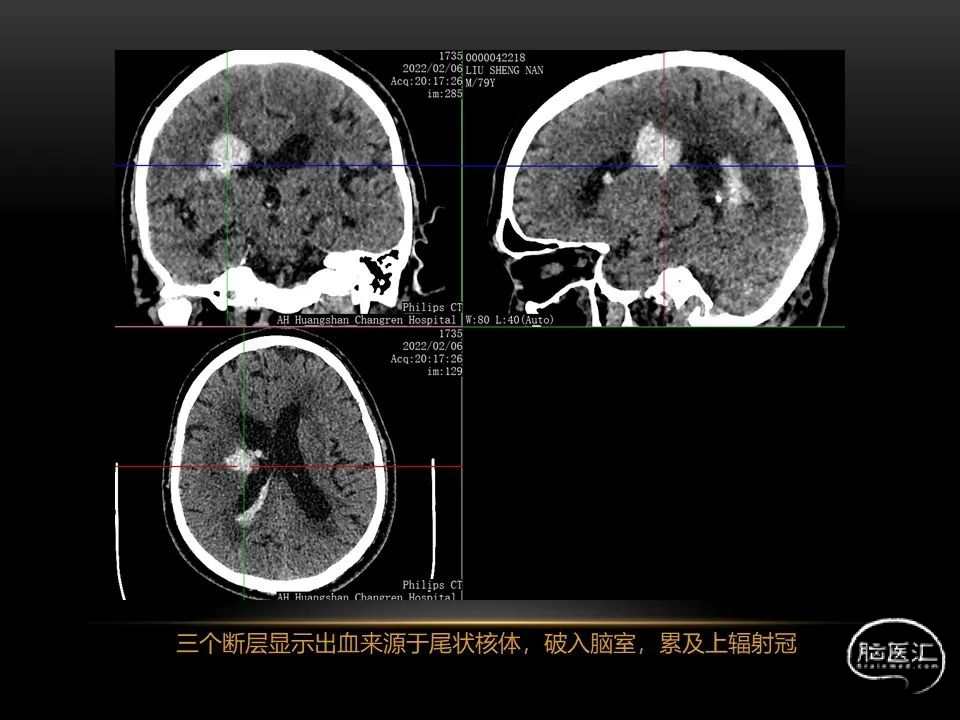

自发性脑出血临床上很常见,不同原因有特征性的出血部位。例如:基底节出血和丘脑出血大多是高血压性脑出血;脑叶出血,特别是多次复发的脑叶出血多见于老年人的脑血管淀粉样变。

自发性脑出血不仅仅累及内囊后肢才会出现偏瘫及偏身感觉障碍,病变累及大脑脚或辐射冠同样有可能有类似症状和体征。内囊、辐射冠、大脑脚等结构之间是延续的,只是不同区域不同名称而已。定位诊断需要对解剖结构概念清晰,读片准确辨认,灵活掌握。